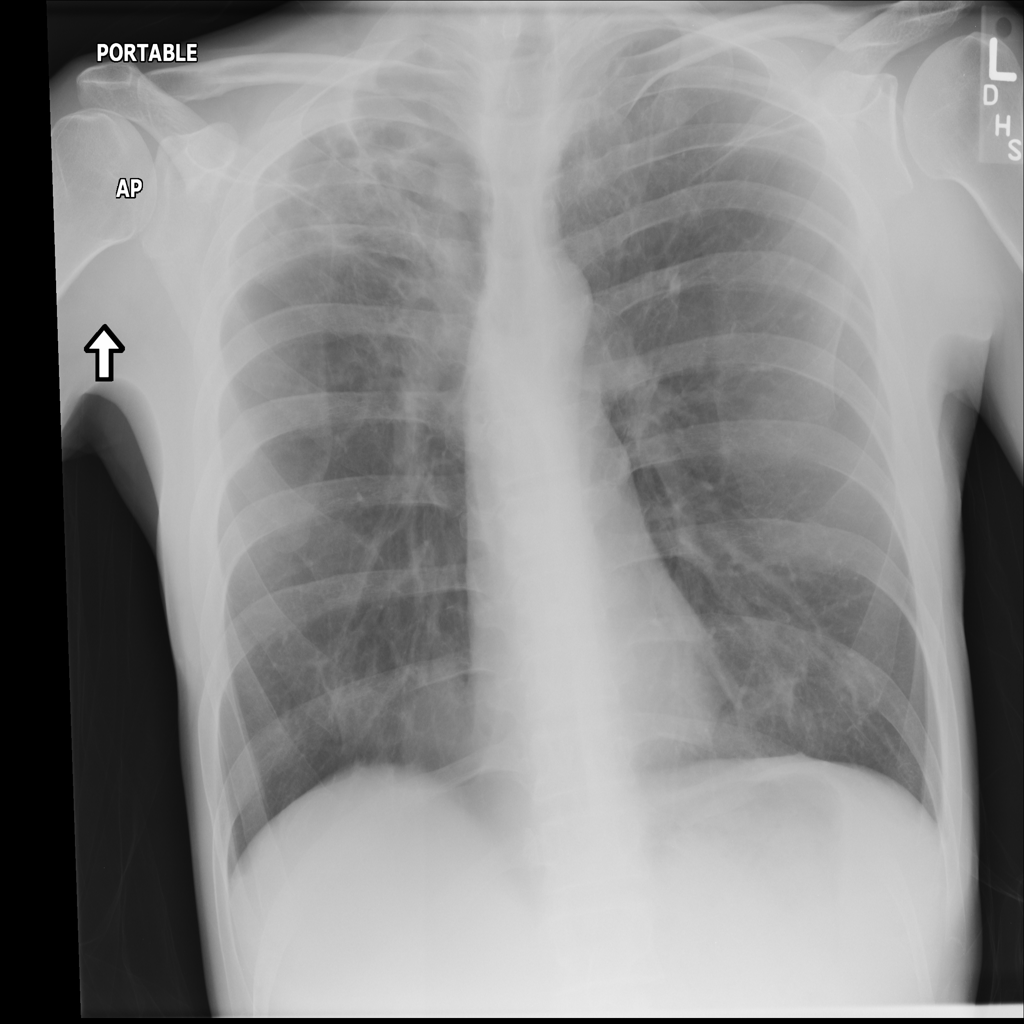

Consolidation

Consolidation refers to air-space filling that makes part of the lung appear denser on imaging.

Showing up to 90 reference images for Consolidation.

PAT-C1A7 · IMG-004Consolidation

PAT-C1A7 · IMG-004

PA